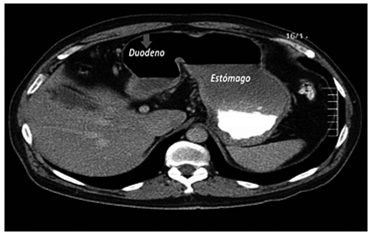

Por esta sintomatología, se le practicó una TC abdómino-pélvica con contraste una semana antes en otra institución, en la cual se informó dilatación de la cámara gástrica, duodeno y yeyuno proximal, con cambio de calibre abrupto a ese nivel, sin evidencia de otros hallazgos (figuras 1 y 2).

Por esto, se utiliza más la tomografía computadorizada (TC), pues es muy sensible para detectar el tumor primario. Se observa generalmente como una lesión focal, irregular, estenosante, con engrosamiento mural, heterogénea, con realce en la fase contrastada y que, en ocasiones, puede disminuir la luz e incluso causar obstrucción intestinal; algunas veces se pueden observar lesiones ulceradas o polipoides. Además, la TC es útil para evaluar la extensión tumoral local y a distancia; las metástasis son más frecuentes en el hígado y se manifiestan como lesiones hipodensas con buen realce en la fase portal 21,22.